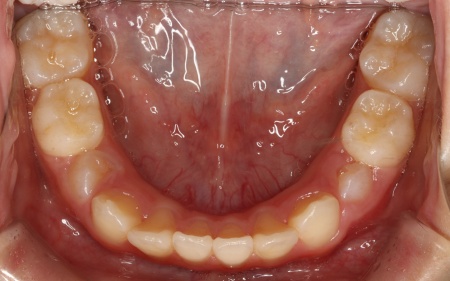

上顎の幅が整ったら、インビザラインファーストによる歯列の調整を開始します。

定期的に通院いただいてマウスピースの適合状態を確認し、計画通り歯が移動しているかを丁寧にチェックしました。

併せて、就寝時には前方牽引装置を使用していただいています。

後日、噛み合わせや歯並びが整ったことを確認し、矯正治療を終了しました。

現在は、3ヶ月に1回のペースで来院いただきながら経過観察を続け、永久歯の生え変わりに合わせて、必要に応じてリテーナー(保定装置)の調整も行っています。